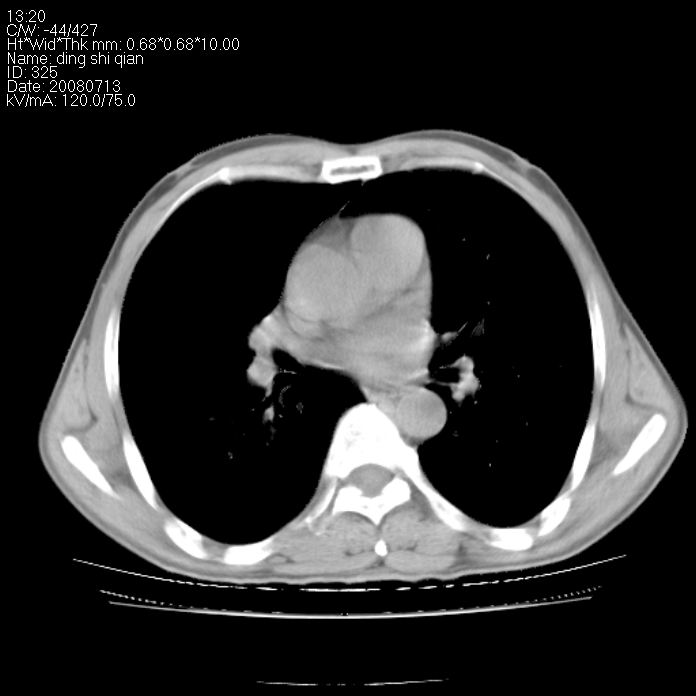

标题: CT14654:男 50岁 近来胸痛 [打印本页]

标题: CT14654:男 50岁 近来胸痛

右侧上肺块状软组织影,浅分叶,边缘毛刺证,与胸膜粘连,考虑:周围性肺癌

右侧上肺块状软组织影,浅分叶,边缘毛刺证,与胸膜粘连,考虑:周围性肺癌!支持!